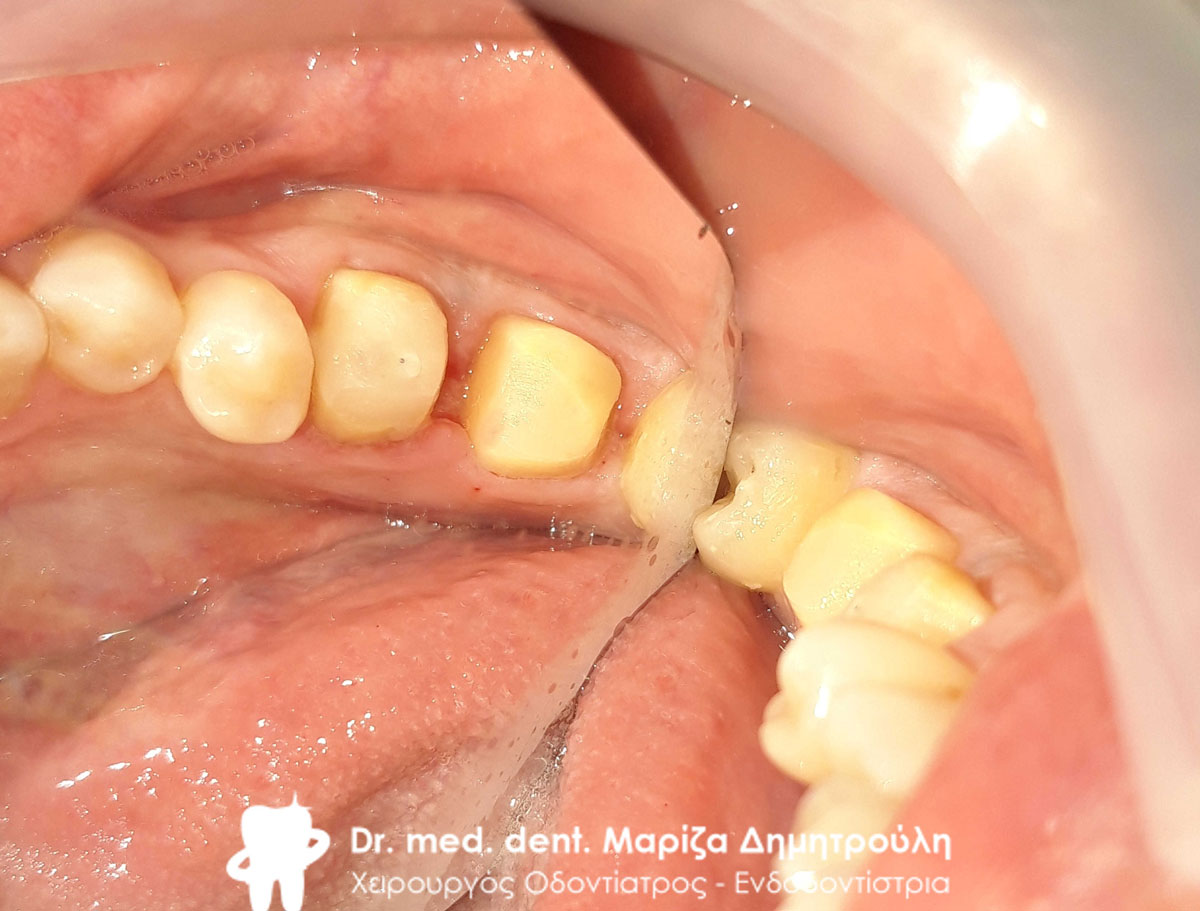

Ο ασθενής είχε δύο παλιές μεταλλοκεραμικές θήκες, οι οποίες με την πάροδο του χρόνου τερηδονίστηκαν, φθάρθηκαν (είχε φθαρεί η κεραμική κάλυψη των θηκών) και έπρεπε να αντικατασταθούν με νέες (απουσιάζει η φωτογραφία της αρχικής εικόνας). Εφόσον αφαιρέθηκαν οι παλιές θήκες πραγματοποιήθηκαν όλες οι απαραίτητες οδοντιατρικές εργασίες (απονεύρωσεις δοντιών, ανασύστασεις / σφραγίσματα δοντιών) όπου ήταν απαραίτητο, προκειμένου να κατασκευαστούν νέες ολοκεραμικές θήκες ζιρκονίου.

Στο μεσοδιάστημα που μεσολάβησε ώστε ο οδοντοτεχνίτης να κατασκευάσει τις νέες θήκες δοντιών, τα τροχισμένα δόντια ήταν προστατευμένα με προσωρινές στεφάνες.

Η νέα γέφυρα είχε ένα πολύ καλό αισθητικό και λειτουργικό αποτέλεσμα.

Αρχική εικόνα των δοντιών μετά την αφαίρεση της παλιάς γέφυρας

Τα δόντια μετά τις απαραίτητες απονευρώσεις και τις ανασυστάσεις